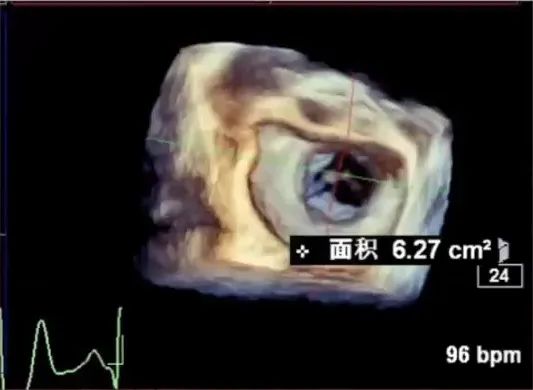

进一步评估患者病变情况,前叶长度2.74mm,后叶长度1.93mm;房间隔前后径4.0cm,房间隔长径6.9cm,瓣口面积6.27cm²,平均跨瓣压差5mmHg。

MVA:6.27CM²

PG:5mmHg